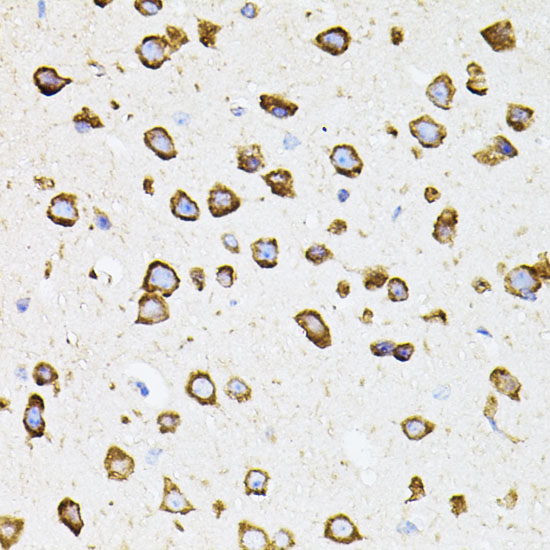

Immunohistochemistry of paraffin-embedded mouse brain using IRF1 (40x lens).

IHC 1:50 - 1:100